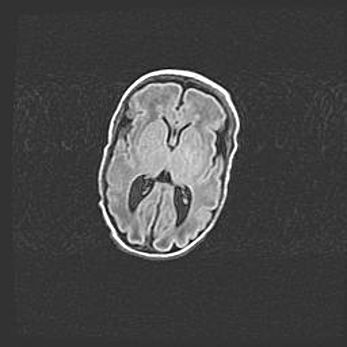

Сообщающаяся гидроцефалия. Кистозная энцефаломаляция головного мозга.

Возраст: 3 месяца 4 дня

Вес: 3100 г

Пол: женский

Окружность головы: 34 см

Срок гестации: 31 неделя

Кистозная энцефаломаляция головного мозга - одна из форм поражения головного мозга в детском возрасте. Характеризуется возникновением множественных и распространённых кист в коре, белом веществе и подкорковых образованиях головного мозга у плодов, новорождённых и детей раннего возраста. Развитие кистозной энцефаломаляции связано с внутриутробной асфиксией и гипотонией, родовой травмой, тромбозом синусов, пороками развития сосудов, инфекциями, сепсисом и другими причинами. Наиболее значимые инфекционные агенты: вирусы простого герпеса, цитомегалии, краснухи, токсоплазмы, энтеробактерии, золотистый стафилококк и другие.